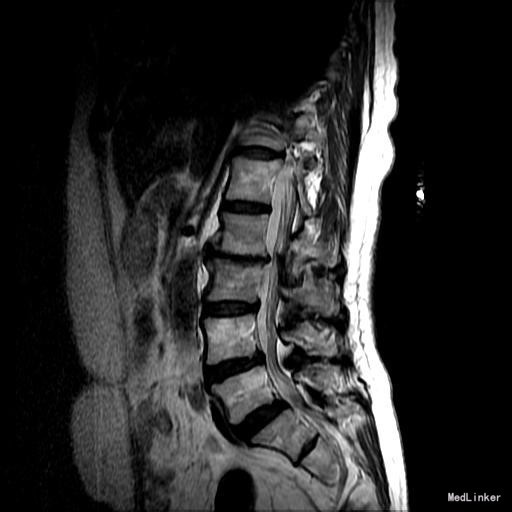

主诉:右下肢麻木11年,腰部酸痛无力 现病史:女性患者,65岁,患者于11年前无明显诱因下出现右下肢麻木,自大腿至右踝部,站立位加重。未予重视,后期出现腰臀部僵硬,弓背僵硬无力,自主行走距离不足200米,曾于06年经X线平片及MRI检查:腰椎椎管狭窄伴有腰椎滑脱,椎间盘突出等。

查体:侧弯畸形,右臀部及右下肢麻木疼痛,腰部活动受限,难以站立。右侧支腿抬高试验60°。双下肢肌力肌张力可。 辅助检查:平片:腰椎侧弯,椎体滑脱,曲度后凸 磁共振:L2-3,L4-5,L5-S1腰椎椎管狭窄,l2-3L3-4L4-5L5-S1腰椎间盘突出,腰椎退变

诊断: 腰椎侧弯,腰椎间盘突出 治疗:1期微创侧路椎体融合术+2期 微创后路经皮内固定术